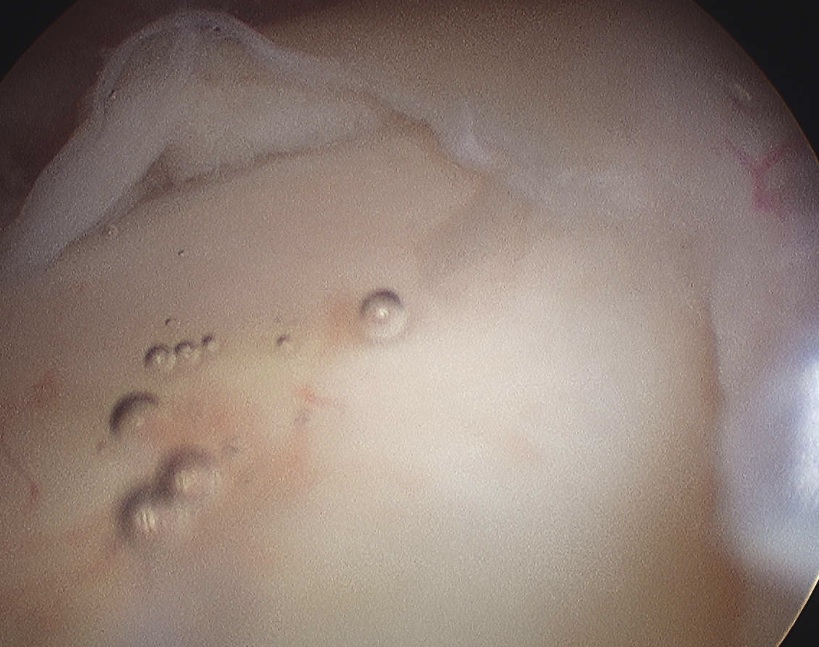

Glenoid assessment

Shoulder Anterior Glenoid Deficiency

Anterior chondral damage

Glenoid Bone LossGlenoid Bone Loss Measurement 1Glenoid Bone Loss Measurement 2

Anterior glenoid bone loss